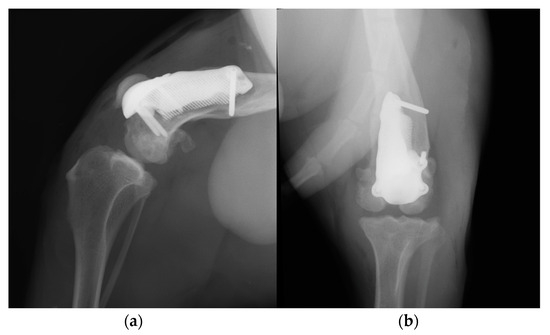

Postoperative medio-lateral and caudo-cranial radiographs of the stifle joint were performed to evaluate the proper prosthesis position and the length of the screws and to confirm the patellar reduction (Figure 10). To improve the postoperative assessment, CT scans of the right stifle joint were obtained. A modified Robert Jones splint was applied for 24 h postoperatively. Meloxicam (0.1 mg/kg) once a day and amoxicillin and clavulanic acid (20 mg/kg) twice a day were prescribed for 10 days, pending the results of a bacteriological examination, and only short walks on the leash to be gradually increased during the two months of postoperative rehabilitation were recommended. After 5 days, the bacteriological exam results were negative, and the antibiotic therapy was continued as indicated previously.

Figure 10. Postoperative medio-lateral (a) and caudo-cranial (b) radiographs of the stifle joint showing the appropriate prosthesis position, the correct length of the screws and the reduction in the patella.